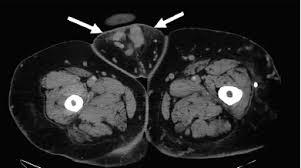

It happens when the blood vessels in and around the pelvis become enlarged. Chronic Pelvic Pain in Women It is estimated that one-third of all women will experience chronic pelvic pain in their lifetime. Pelvic congestion syndrome PCS is a chronic condition that occurs in women when varicose veins form below the abdomen within the pelvic.

Typical age effected is between 20 and 45 years old. Veins are the blood vessels that carry blood back to the heart. In both cases the valves in the veins that help return blood to the heart against gravity become weakened and dont close properly.

First described by Richet in 1857 the symptoms of chronic dull pelvic pain pressure and heaviness are often a result of dilated tortuous and congested veins produced by retrograde flow through incompetent valves in ovarian veins 39 41 Fig 18. Pelvic congestion syndrome PCS is characterized by chronic pelvic discomfort exacerbated by prolonged standing and coitus in women who have periovarian varicosities on imaging studies. It is thought to be caused by problems with the veins in the pelvic area.